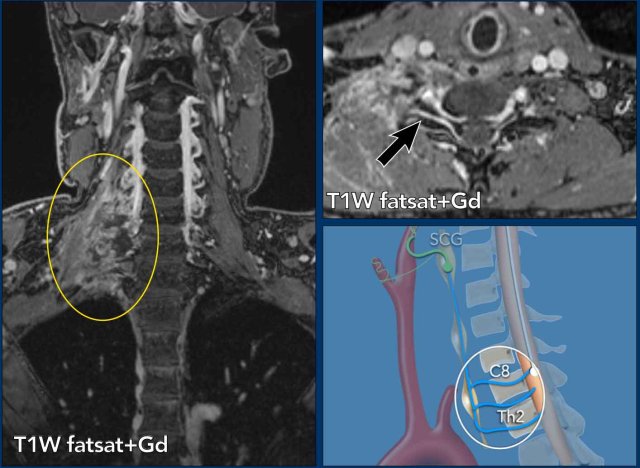

Case

45 year-old man with sudden onset Horner syndrome, dysphagia, ipsilateral ataxia, nystagmus and sensory impairment ipsilateral face and contralateral body.

Images

Diffusion weighted images DWI (B1000) and ADC images show restricted diffusion in the medulla oblongata on right side due to a lateral medullary infarction.

Continue with the MRA of the neck...

Contrast enhanced MRA of the neck (on the right) shows narrowing of the right vertebral artery .

The T1WFS-image of the neck shows a  hyperintense crescent signal intensity in the wall of the right vertebral artery typical of an intramural hematoma.

Conclusion

Dissection of the right vertebral artery resulting in a medullary infarction.